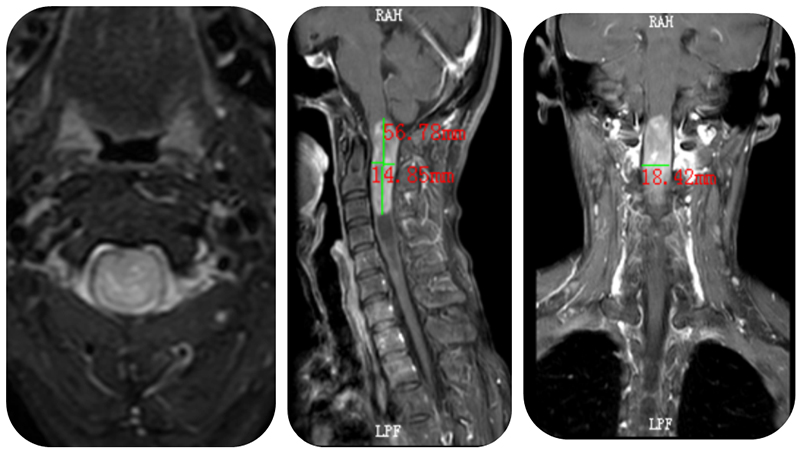

近日,我院神经外科副主任胡栓贵带领团队成功为一名身患脊髓髓内肿瘤的患者完成手术,在全显微镜下将56×18×15毫米的脊髓髓内室管膜瘤完全切除,解除了深藏患者体内的定时炸弹。

胡栓贵副主任介绍,农阿姨脊髓髓内的肿瘤为室管膜瘤,是脊髓髓内常见的肿瘤。正常的脊髓中央有一个狭窄的管道,称为中央管,该中央管的内表面有一层由室管膜细胞围成的上皮样膜,称为室管膜。室管膜瘤就是来源于这层室管膜细胞的肿瘤。农阿姨脊髓内的肿瘤的尺寸为56×18×15毫米,肿瘤占据了中央管大部分位置,脊髓受压变薄造成了她的症状。

术前MRI显示肿瘤肿瘤的直径已经大于正常脊髓的直径

术前(图1、图3)与术后(图2、图4)对比